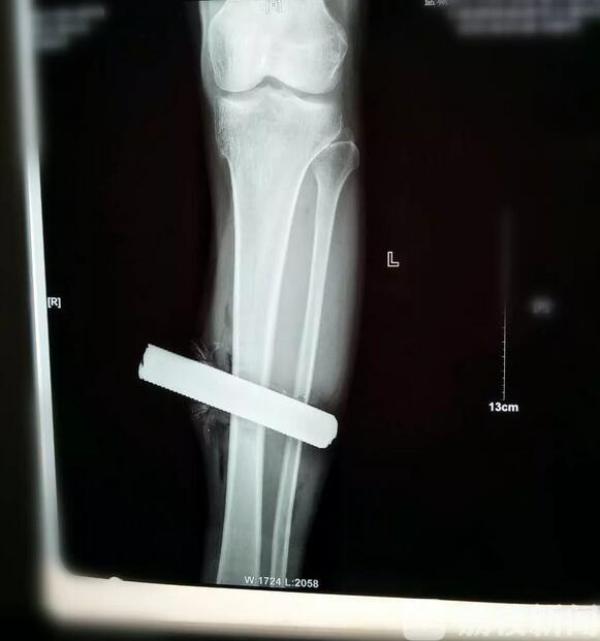

在医院看到患者小腿被钢筋完全贯通,伤后即感左小腿下端剧烈疼痛,左踝活动受限,不能站立行走,左小腿远端肿胀。急诊医生迅速安排拍片等检查,手术迫在眉睫。

上午10:51,患者被送到手术室。经过医护团队的充分准备,顺利取出伤者腿上的钢筋,之后又进行了清创、冲洗。

据手术的倪生华主治医师介绍,不幸中的万幸钢筋没有伤到骨头,但是贯穿也造成肌腱以及肌肉断裂;钢筋上有大量的铁锈、油渍、泥沙,需要反复冲洗,不能有一丝遗漏,不然很难避免感染等并发症。历时1个半的手术终于结束了。伤者现在病情稳定,一周后再进行一个小手术就可以选择出院了。